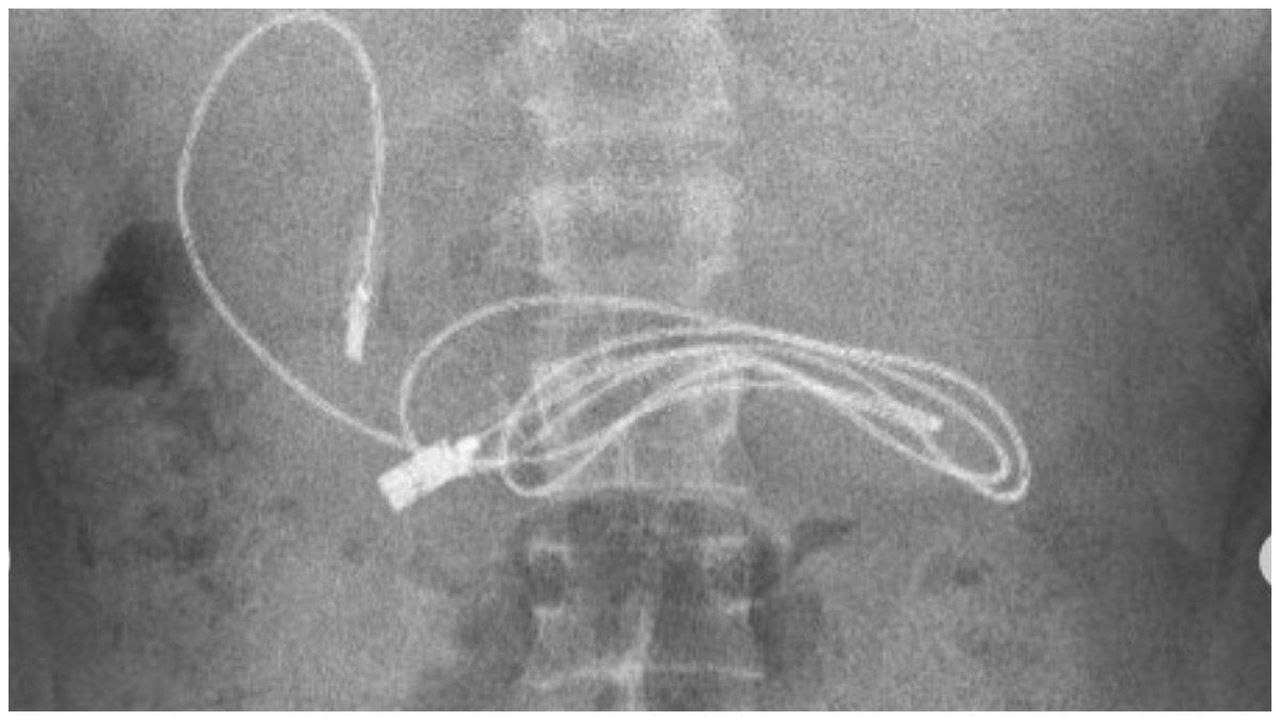

Tras revisar al joven que llegó por un dolor y hacerle una radiografía, los doctores encontraron un cable de carga en su estómago.

Procedimiento que les ayudó para extraerle al joven una cinta para el cabello y un cable de carga que alcanzó el metro de longitud cuando se estiró.

De acuerdo con el Dr. Dogan, y el equipo de doctores que trataron el caso del joven que tenía un cable de carga en su estómago, la extracción fue algo complicada.

En declaración para medios locales, el médico explicó que el procedimiento no resultó sencillo, ya que el cable había pasado al intestino delgado.